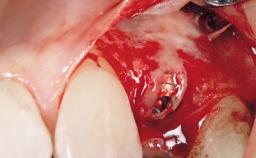

A 30-year-old female patient had lost tooth 21 and was referred to our clinic for consultation and treatment. Due to advanced apical infection, tooth 21 had been extracted two months earlier at another clinic and an acrylic-resin tooth had been bonded to the adjacent teeth. The patient desired implant treatment to avoid any damage to the adjacent natural teeth. While the patient had no history of any systemic disorder, she was a heavy smoker and exhibited medium to advanced periodontitis in the entire jaw. After the initial treatment to achieve a pocket probing depth of less than 4 mm and no bleeding on probing, a decrease in the height of the papillae mesial and distal to the extraction site and overall gingival recession were observed.

| Bone Augmentation | Horizontal|Staged |

| Augmentation Materials | Autogenous chips|Membrane |

| Soft Tissue Grafting | Simultaneous |